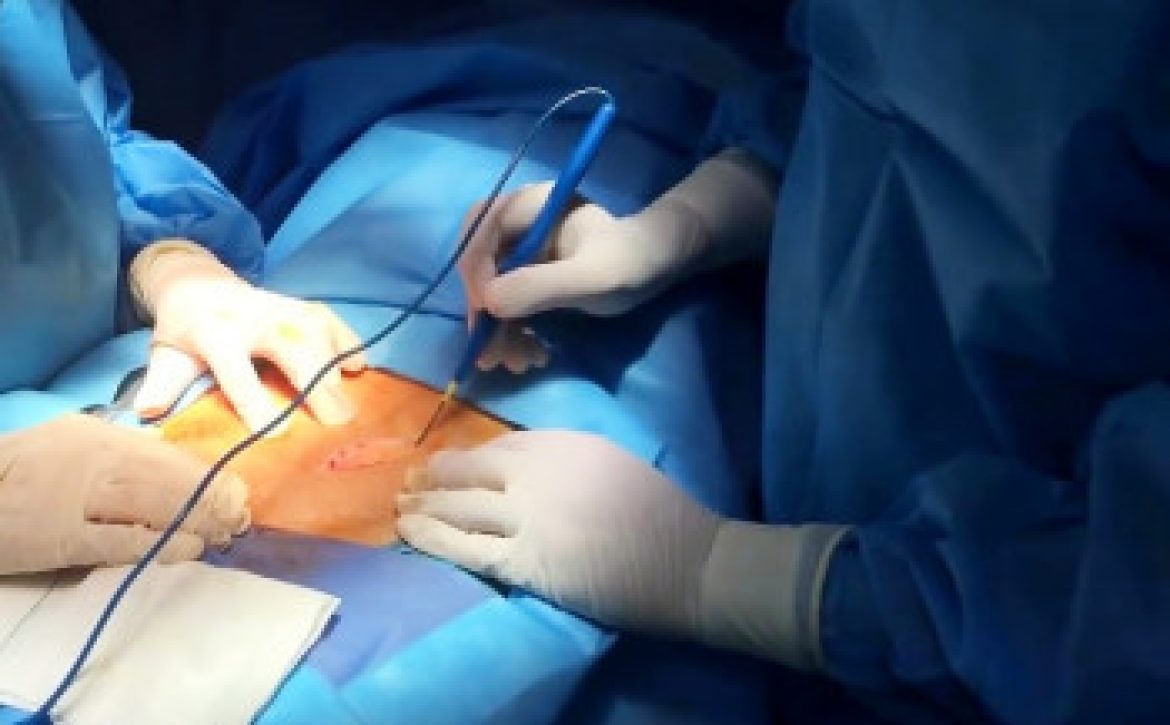

جراحی

اگر بیمار به درمانهای دارویی پاسخ مناسبی ندهد، گزینه جراحی مطرح میشود که شامل قطع عصب واگ یا برداشتن بخشی از معده (گاسترکتومی جزئی) است.\[۲]